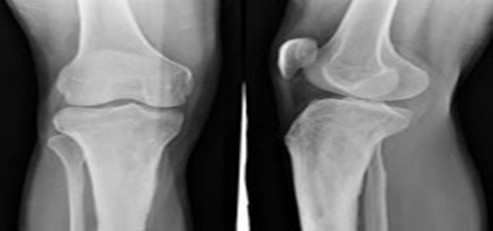

【辅助检查】X线正、侧位片发现骨折及移位。